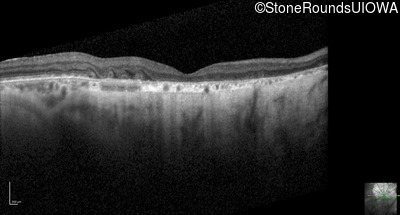

Optical Coherence Tomography - Left - 20/200

Exemplar / OCT Stack